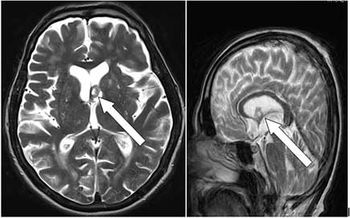

Case History: 15-month-old with focal seizure, developmental delay, disproportionate increase in size of head.

Published: January 10th 2017 | Updated: